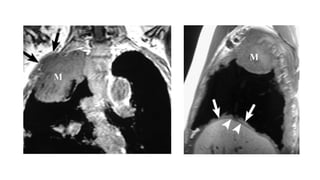

Resonancia magnética

• Se debe realizar RM en aquellos casos en los que la TAC con contraste esté

contraindicada o cuando la infiltración extrapleural no se demuestre

claramente con esta técnica.

• La RM es especialmente útil en los casos en que la enfermedad sea

potencialmente resecable y nos puede proporcionar información adicional

sobre el estado de los márgenes tumorales y la afectación del diafragma,

fascia y pared torácica.

HALLAZGOS EN LA RM

• Pérdida de los planos grasos

• Afectación circunferencial de más de 50% de las estructuras mediastínicas

• Afectación de la grasa mediastínica

• Invasión del diafragma

• Invasión de la fascia endotorácica

T1=================Isotenso o discretamente hiperinteso

T2=================Moderadamente hiperintenso

T1 + Gadolinio=======Realce intenso

Diagnóstico: Resonancia magnética • Sedebe realizar RM en aquellos casos en los que la TAC con contraste esté contraindicada o cuando la infiltración extrapleural no se demuestre claramente con esta técnica. • La RM es especialmente útil en los casos en que la enfermedad sea potencialmente resecable y nos puede proporcionar información adicional sobre el estado de los márgenes tumorales y la afectación del diafragma, fascia y pared torácica.

HALLAZGOS EN LARM • Pérdida de los planos grasos • Afectación circunferencial de más de 50% de las estructuras mediastínicas • Afectación de la grasa mediastínica • Invasión del diafragma • Invasión de la fascia endotorácica T1=================Isotenso o discretamente hiperinteso T2=================Moderadamente hiperintenso T1 + Gadolinio=======Realce intenso